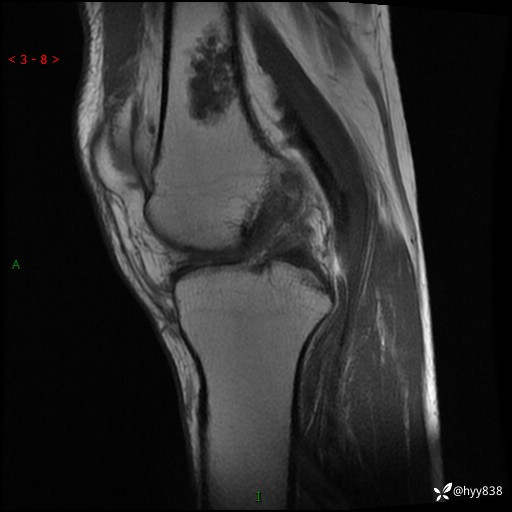

患者性别:男

患者年龄:60岁

主诉:右大腿疼痛不适数月

膝关节平片

MRI

内生软骨瘤 (27)